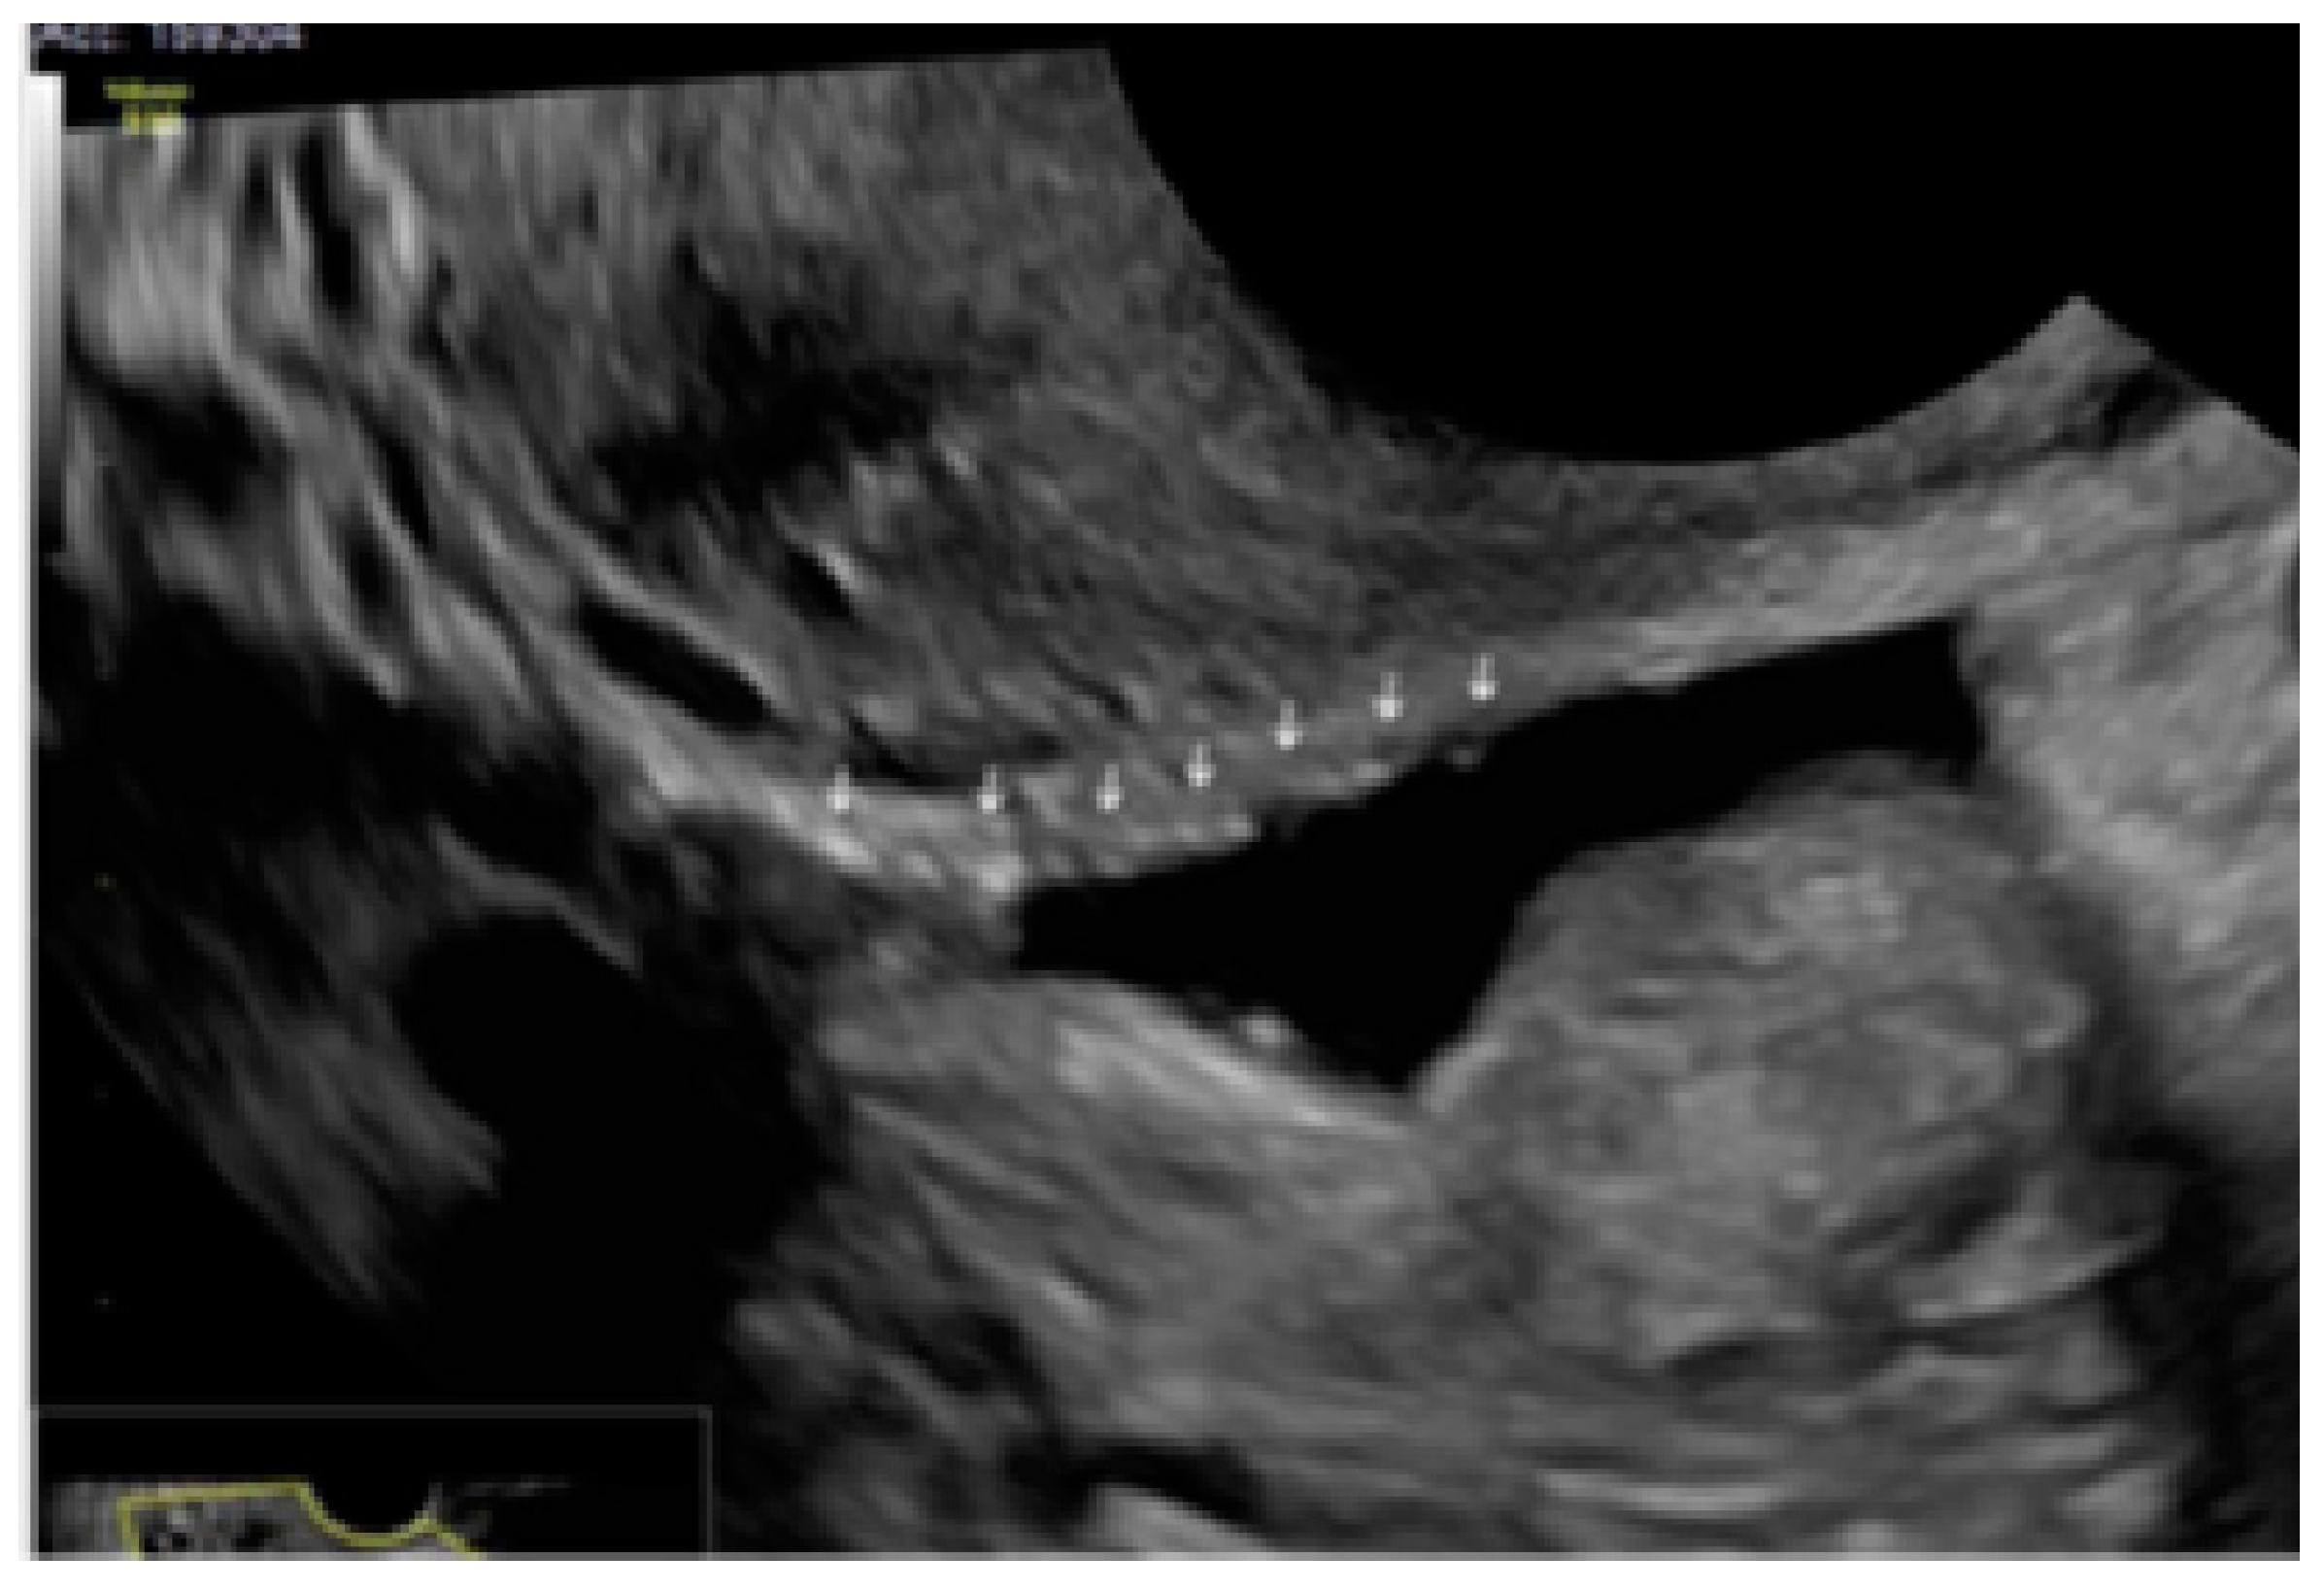

- The presence of velamentous (filmy) adhesions associated to the lesion (we called this a “veil”).